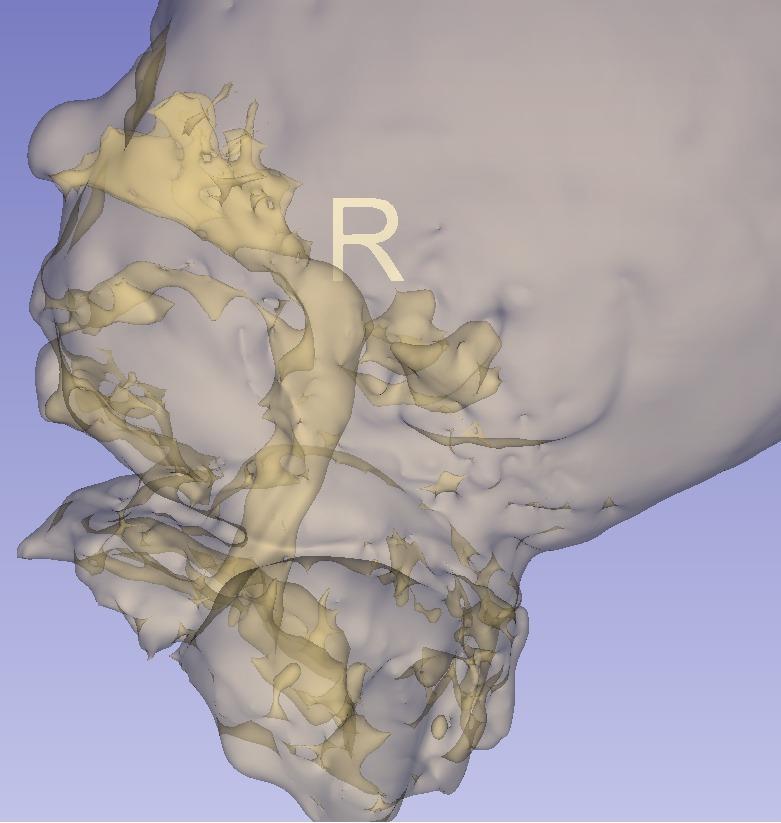

Cristina Felice Civitillo (1), Frédéric Jonathan Leis (2), Céline Habre (3), Francisca Barcos- Munoz (1) (1) Néonatologie et soins intensifs pédiatriques, Département Femme Enfant et Adolescent, HUG, Hôpitaux Universitaires de Genève (2) Atelier 3Durable, Université de Genève (3) Département de Diagnostic, Service de Radiologie, HUG, Hôpitaux Universitaires de Genève

IRM de vrais patients → Voies aériennes (bouche-trachée)

Différents âges gestationnels (24 - 44 SA) et différents poids (400g - 4kg)

Impression 3D multi-matériel

Création simulateur haute fidélité pour intubation